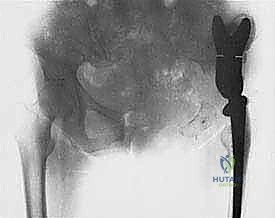

2. إعادة بناء وتثبيت العظم والمفاصل المصابة (Reconstruction)

بمجرد إزالة الورم والفراغ العظمي الكبير، يبدأ بناء الطرف الجديد. هنا يأتي دور أنظمة الأطراف الاصطناعية الداخلية.

* يتم تحضير القنوات النخاعية للعظام المتبقية.

* يتم إدخال سيقان الغرسة (إما باستخدام الأسمنت العظمي الطبي للتثبيت الفوري، أو سيقان غير أسمنتية مغطاة بمواد مسامية تسمح للعظم الطبيعي بالنمو داخلها والالتحام بها).

* يتم تجميع القطع المعيارية لتعويض الطول الدقيق للعظم المفقود.

* يتم ربط آلية المفصل الجديد (مثلاً، مفصل ركبة مفصلي Hinge joint يوفر الاستقرار الكامل).